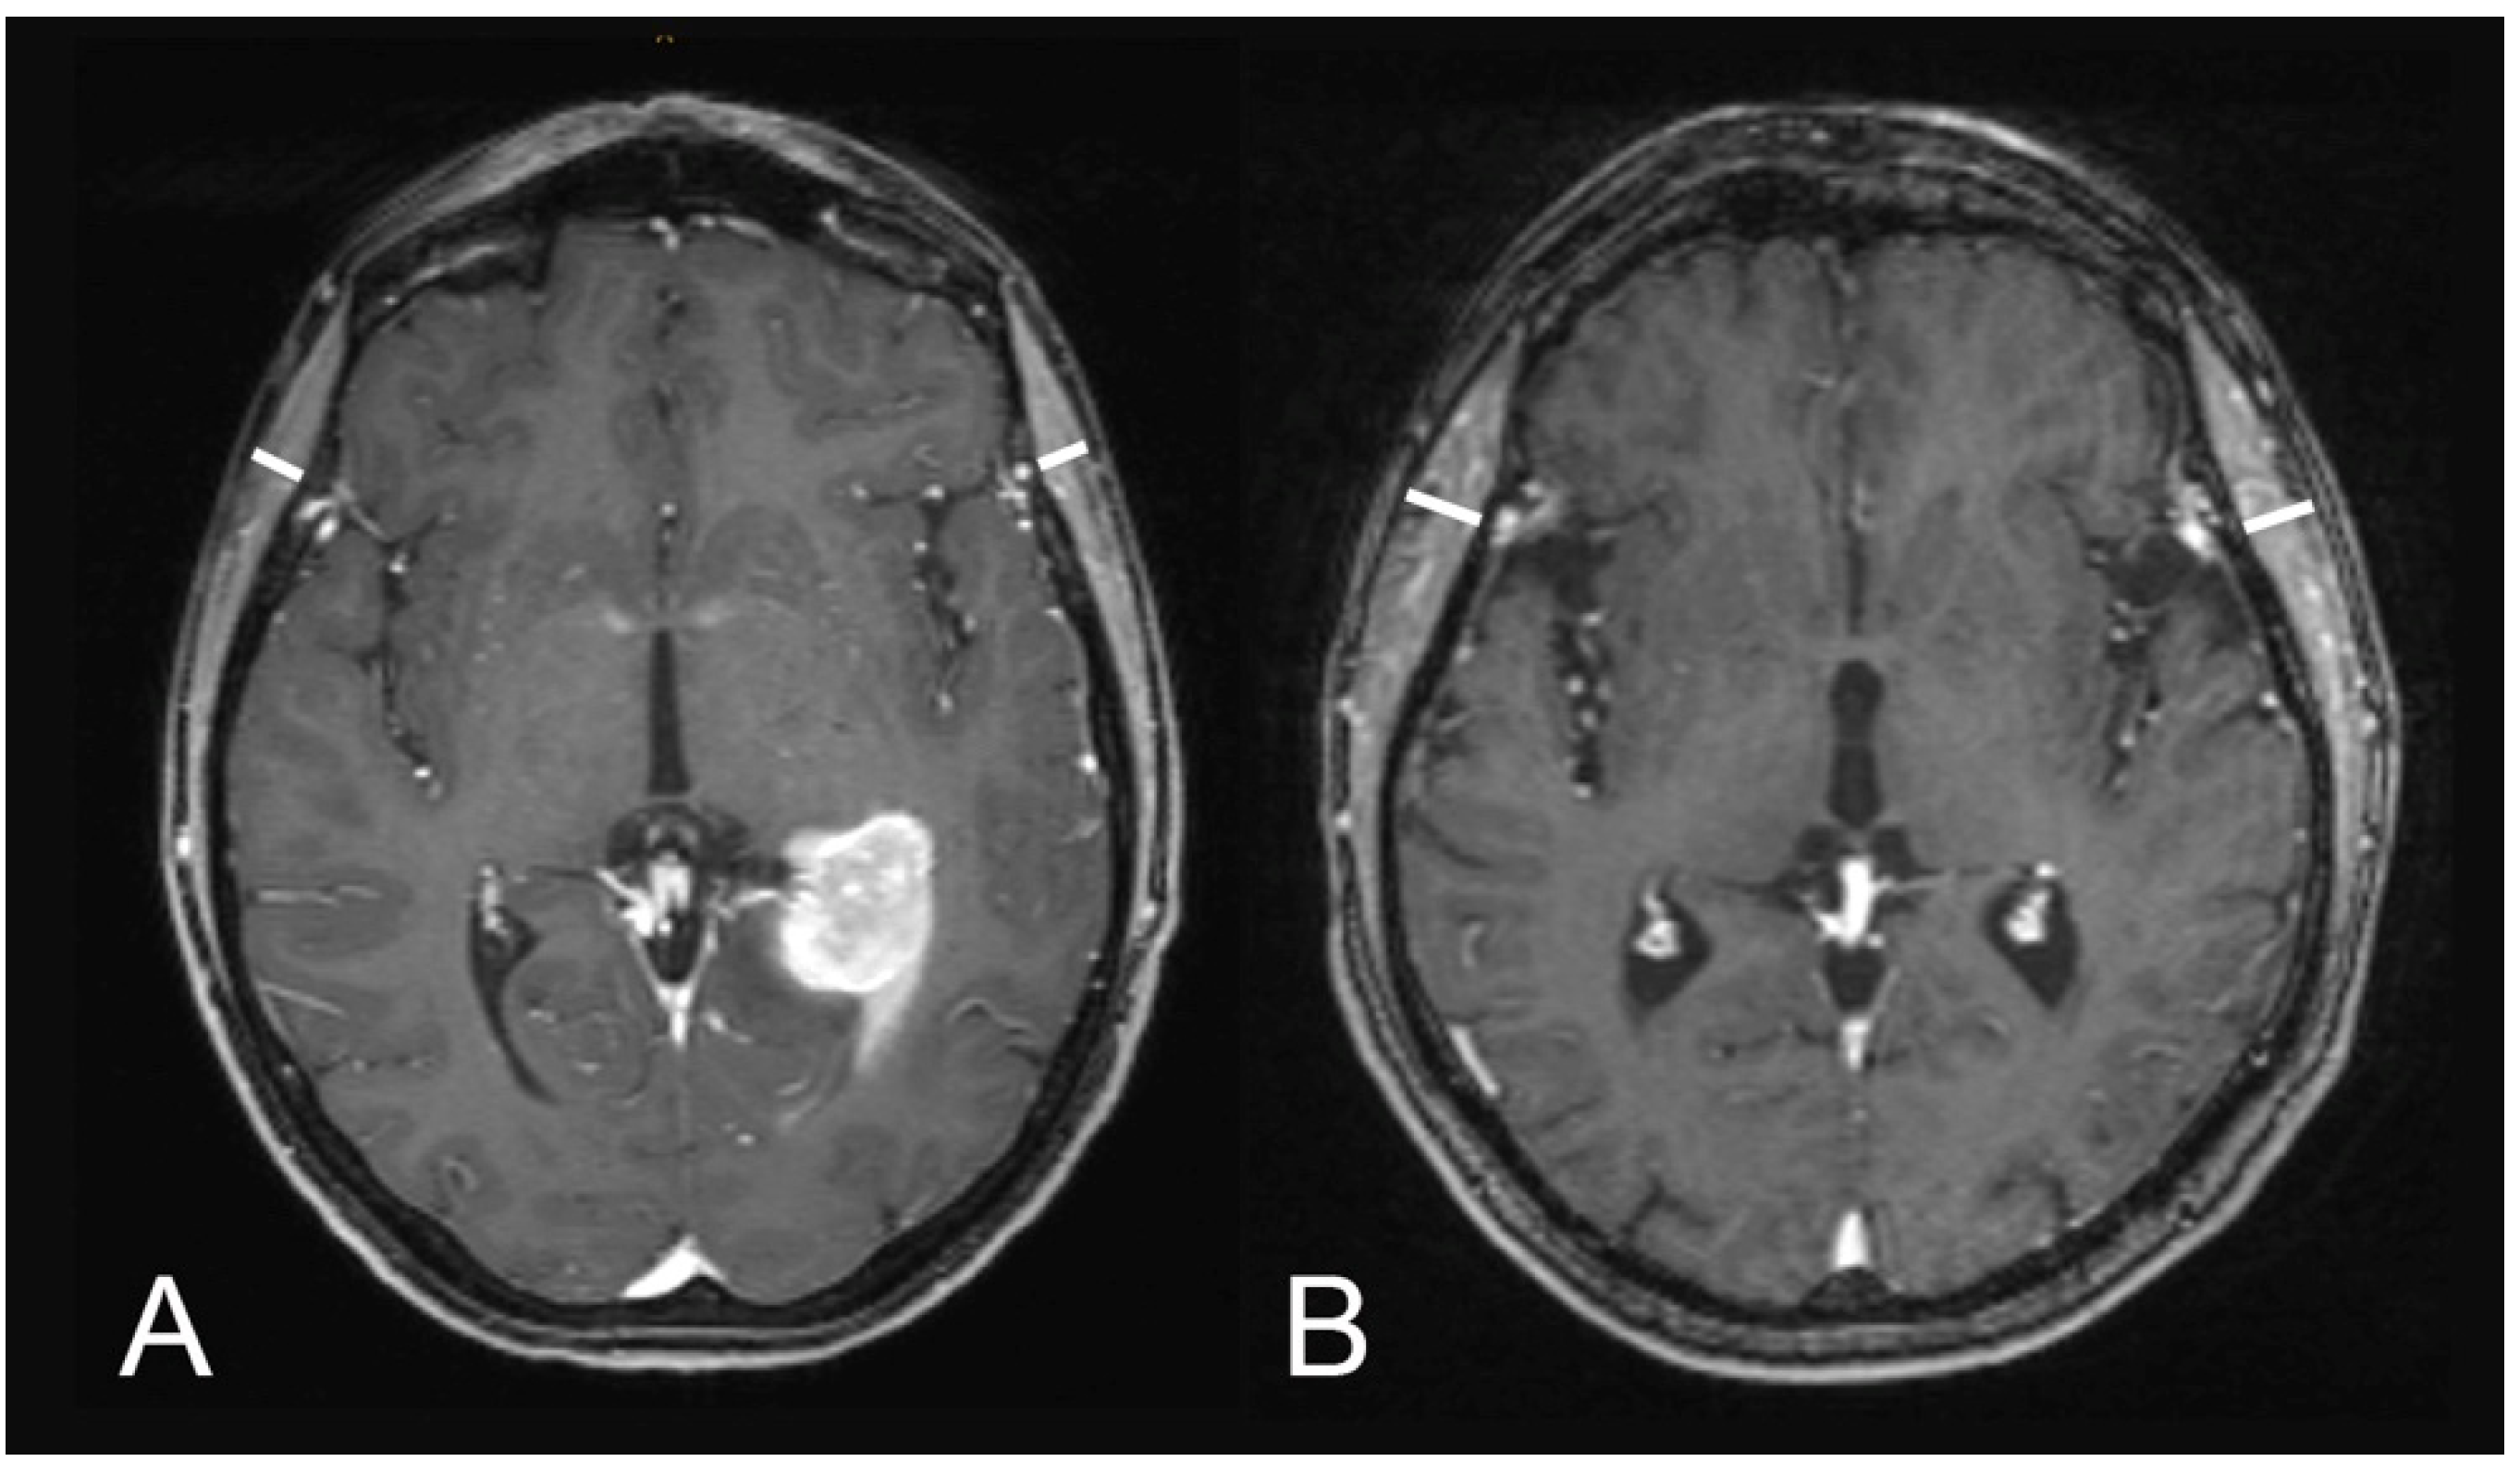

Figure 1 illustrates examples of TMT measurements on T1-weighted contrast-enhanced MR images.

Figure 1.

Illustration of TMT assessments on T1-weighted contrast-enhanced magnetic resonance images: (A) a 60-year-old male patient with an overall survival of one month (median TMT = 5.75 mm) and (B) a 51-year-old male patient with an overall survival of 73 months (median TMT = 8.1 mm).